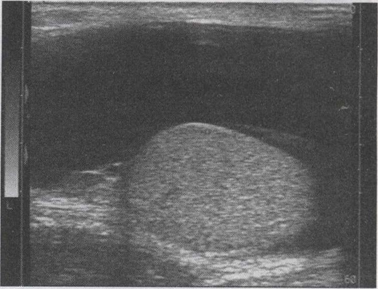

38.某患者阴囊超声声像图如下,最可能的诊断为()